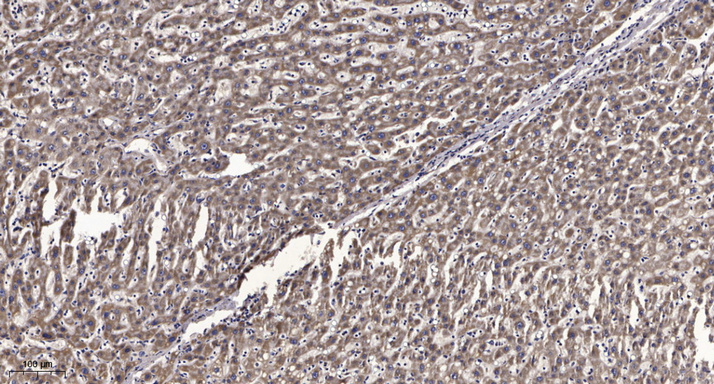

IHC (Immunohistochemistry)

(Immunohistochemical analysis of paraffin-embedded human liver cancer. 1, Antibody was diluted at 1:200(4 degree overnight). 2, Tris-EDTA,pH9.0 was used for antigen retrieval. 3,Secondary antibody was diluted at 1:200(room temperature, 45min).)